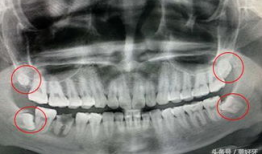

你知道吗?拔智齿这个话题,最近在网络上可是火得一塌糊涂呢!很多人都在好奇,拔智齿到底是个啥样的过程,是不是像传说中的那么恐怖?今...